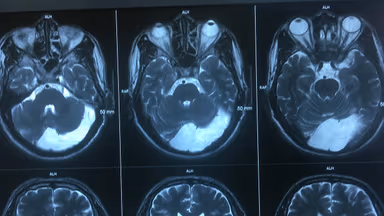

Kết quả chụp cộng hưởng từ MRI não của cô N. phát hiện hình ảnh u màng não và nhiều tổn thương. Cụ thể:

– Hình ảnh u ngoài trục vùng đỉnh trán có tính chất u màng não. Cụ thể: khối u ngoài trục vị trí vùng đỉnh trái kích thước 15x19x21mm, tổn thương tín hiệu không đều, có hạn chế khuếch tán nhẹ, sau tiêm ngấm thuốc mạnh và đồng nhất, có dấu hiệu đuôi màng cứng, khối đè đẩy nhu mô não gây phù não vùng hồi trước và sau trung tâm thùy đỉnh trái.

– Rải rác ổ thoái hóa myelin chất trắng dưới vỏ thùy trán đỉnh bán cầu não hai bên.

– Viêm xoang sàng